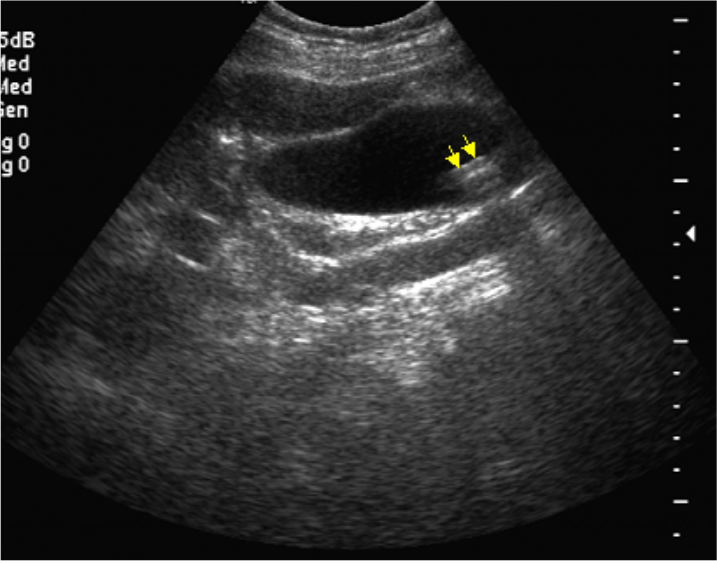

66.45歲女性病人,甲狀腺癌術後回來接受追蹤檢查。下圖為右下側頸部超音波橫切面,黃色箭 號所指為何?

(A)頸動脈 (B)淋巴結腫大 (C)頷下腺 (D)副甲狀腺